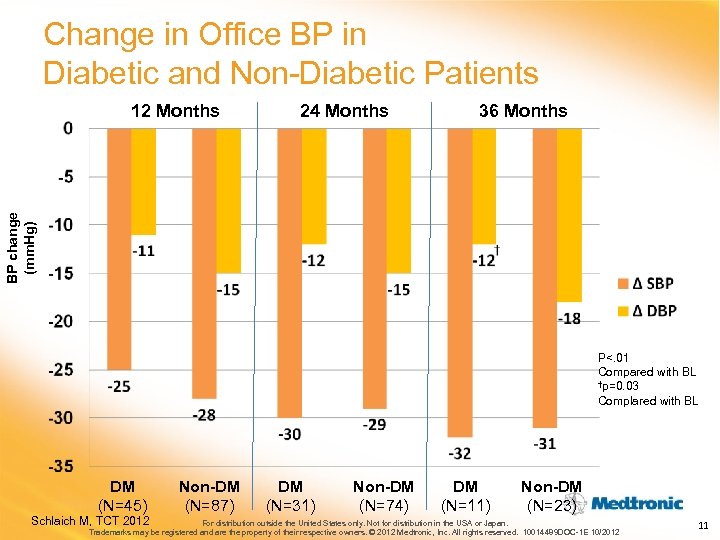

Change in Office BP in Diabetic and Non-Diabetic Patients 24 Months 36 Months BP change (mm. Hg) 12 Months P<. 01 Compared with BL †p=0. 03 Complared with BL DM (N=45) Schlaich M, TCT 2012 Non-DM (N=87) DM (N=31) Non-DM (N=74) DM (N=11) Non-DM (N=23) For distribution outside the United States only. Not for distribution in the USA or Japan. Trademarks may be registered and are the property of their respective owners. © 2012 Medtronic, Inc. All rights reserved. 10014489 DOC-1 E 10/2012 11

Change in Office BP in Diabetic and Non-Diabetic Patients 24 Months 36 Months BP change (mm. Hg) 12 Months P<. 01 Compared with BL †p=0. 03 Complared with BL DM (N=45) Schlaich M, TCT 2012 Non-DM (N=87) DM (N=31) Non-DM (N=74) DM (N=11) Non-DM (N=23) For distribution outside the United States only. Not for distribution in the USA or Japan. Trademarks may be registered and are the property of their respective owners. © 2012 Medtronic, Inc. All rights reserved. 10014489 DOC-1 E 10/2012 11